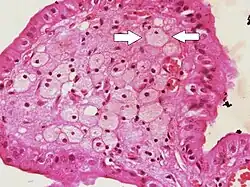

![]() | Fatty change in liver | Hepatic parenchymal cell cytoplasm containing clear vacuoles containing fat of varying sizes, displacing the nucleus towards the periphery. | Category: Lipid steatosis | steatosis |